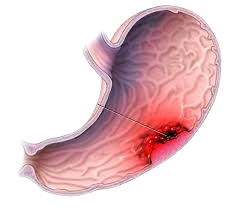

4. Cancer of StomachPain in upper abdomen, fullness after eating small quantity of food (bloating), nausea, poor appetite, vomiting, loss of weight are the presenting symptoms of gastrointestinal cancer. Early diagnosis with endoscopy, often improves prognosis. |